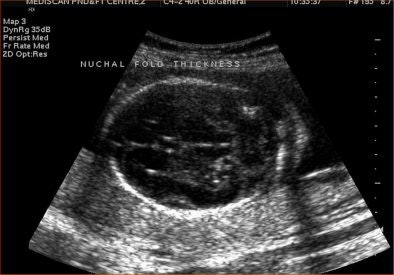

Nuchal fold thickness is the first sonographic marker to have been associated with increased risk of Down syndrome. An increased nuchal fold thickness of 6 mm or higher warrants a fetal karyotype, regardless of associated abnormalities, Suresh said. The nuchal fold thickness should be measured only between 15-20 weeks because the normal skin thickness remains unchanged in this period.

For measuring nuchal fold thickness, a transaxial view of the head is taken through the thalamus, cerebellum, and occipital bone. The nuchal fold thickness is measured in the cerebellar plane from the outer surface of the occipital bone to the outer surface of the skin.

![]() |

| Increased nuchal fold thickness. |

The following table shows how risk for Down syndrome changes depending on whether the ultrasound shows normal or increased nuchal fold thickness in the fetus.

"The most important minor marker is the nuchal fold. Short humerus and echogenic bowel are the second most important markers. EIF, renal pyelectasis, and CP cysts have poor accuracy and limited impact on Down syndrome," Pai said.